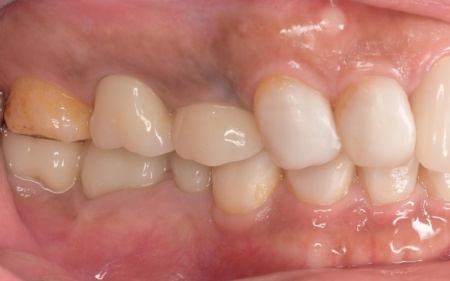

治療後

矯正期間終了後は、被せ物による治療に移行します。

上顎の前歯2本ずつと奥歯4本(左右中切歯・第2小臼歯・第1大臼歯)、下顎の奥歯7本(左第1小臼歯・左右第2小臼歯・第1大臼歯・第2大臼歯)には、見た目が自然なセラミックの被せ物「ジルコニアクラウン」を装着しました。

ジルコニアは、金属を使わないため金属アレルギーの心配が少ない点、人工ダイヤモンドと呼ばれるほどの強度をもち噛む力の強い奥歯にも適している点がメリットです。

加えて、上前歯4本(左右側切歯・犬歯)と下前歯5本(左右中切歯・側切歯・右下犬歯)は、ダイレクトクラウンによる修復を行いました。